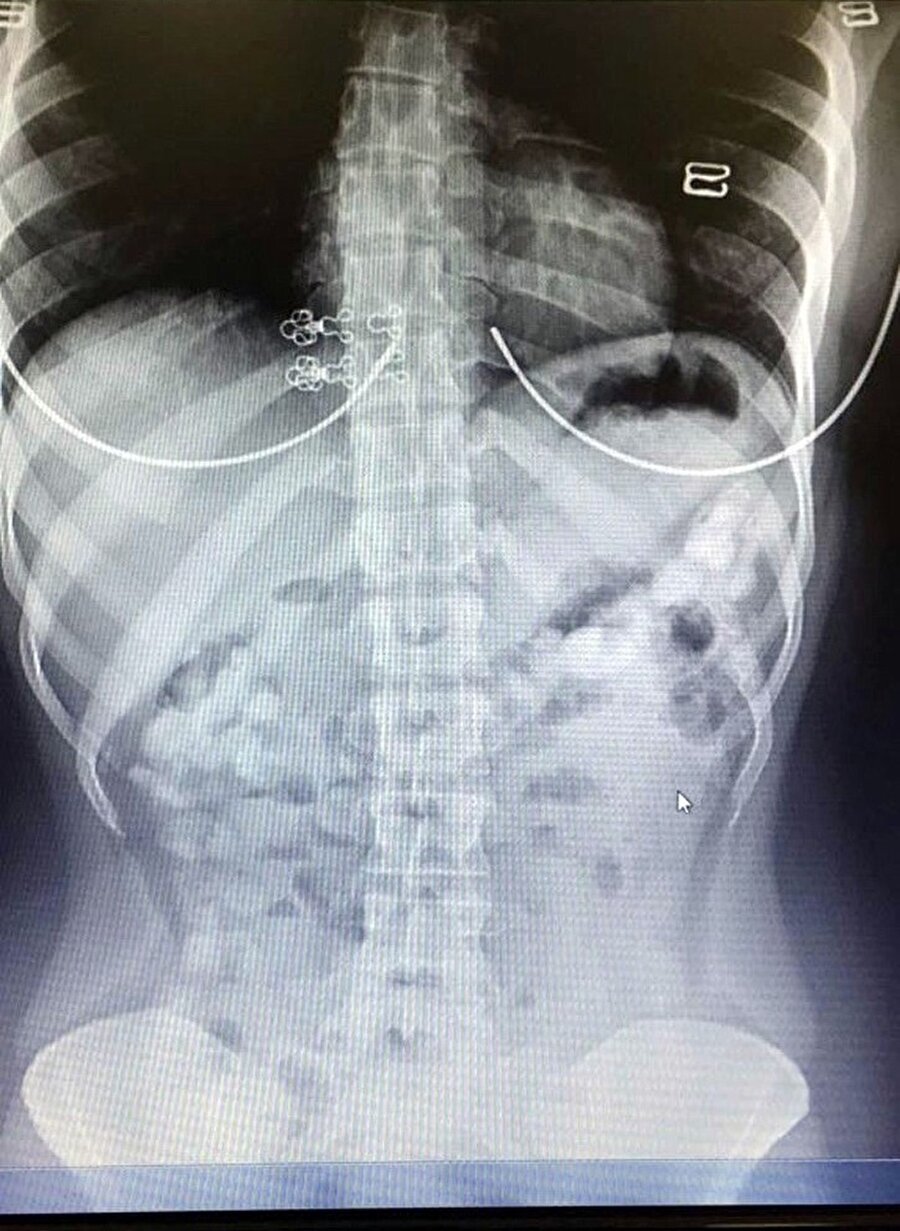

Uyuşturucu maddeleri kapsül halinde yutan 29 yaşındaki Venezüellalı kuryenin iç organlarında çekilen röntgende kokain olduğu görüldü.

Maria Rodriguez’in iç organlarında her biri 10-12 gram ağırlığında 78 kapsül ortaya çıktı. Şüpheliden doğal yollarla 71 kapsül çıkarılırken, Rodriguez’in 5 bin Dolar karşılığında kuryelik yaptığı öğrenildi.